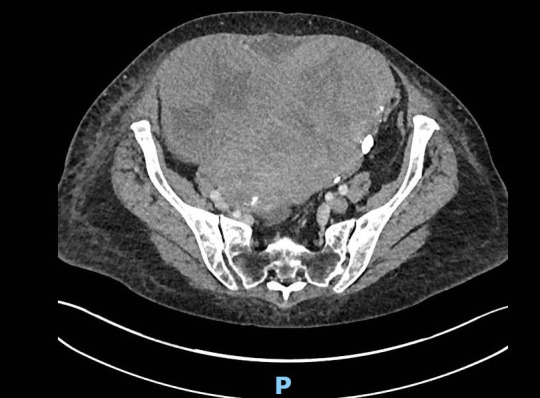

Bilateral pleural effusions, ascites and pulmonary emboli: Meigs syndrome.

Meigs syndrome is associated with unilateral or bilateral pleural effusions, ascites, high CA-125 levels and ovarian fibromas. Concurrent arterial and venous thromboses have also been described. Surgical removal of the fibroma is curative. https://bit.ly/4jZsB4D.